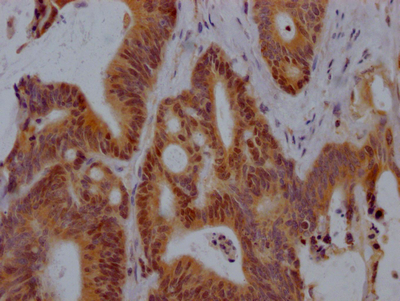

IHC image of CSB-PA10599A0Rb diluted at 1:300 and staining in paraffin-embedded human ovarian cancer performed on a Leica BondTM system. After dewaxing and hydration, antigen retrieval was mediated by high pressure in a citrate buffer (pH 6.0). Section was blocked with 10% normal goat serum 30min at RT. Then primary antibody (1% BSA) was incubated at 4°C overnight. The primary is detected by a biotinylated secondary antibody and visualized using an HRP conjugated SP system.

IHC image of CSB-PA10599A0Rb diluted at 1:300 and staining in paraffin-embedded human breast cancer performed on a Leica BondTM system. After dewaxing and hydration, antigen retrieval was mediated by high pressure in a citrate buffer (pH 6.0). Section was blocked with 10% normal goat serum 30min at RT. Then primary antibody (1% BSA) was incubated at 4°C overnight. The primary is detected by a biotinylated secondary antibody and visualized using an HRP conjugated SP system.